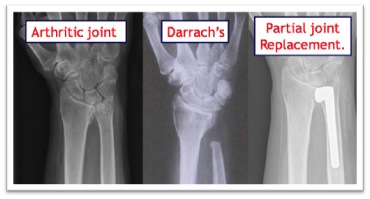

Darrachs . When rheumatoid arthritis affects the DRUJ the ulna head dislocates from the wrist joint and develops a painful lump on the back of the wrist. This can rub on the finger tendons as they pass over the wrist and are at risk of snapping. In rheumatoid arthritis the surgery is aimed at removing the worn out bone which removes the insult on the tendons and the painful arthritic joint. This is called a Darrachs procedure and gives good relief of pain.

Joint replacement . If the arthritis occurs in a younger or high demand patien

t a joint replacement gives better results than removing the ulna head.  This is because a Darrachs procedure in these patients can result in pain when gripping and carrying things as the stump of the remaining ulna bangs into the radius bone.  Only half of the ulna head is involved in the joint itself, the other half has ligaments an

d tendons attached which are vital for stability of the joint.  Recent advances in joint replacement mean that only the worn half of the head is replaced, leaving the ligaments and tendons alone to assist in the proper function of the wrist. The operation is indicated when all non operative measures have been exhausted. An 8cm incision is made in the back of the wrist and the soft tissues are carefully preserved. The stem is placed down the shaft of the bone which fixes it in firmly. The soft tissues are then repaired over he top and skin stitched with absorbable sutures. A small sticky dressing or gauze is used to keep the wound clean and dry. A plaster is applied to protect the joint replacement while the tissues around it heal.